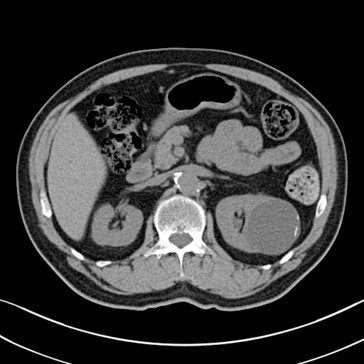

bosniak classification?

bosniak I

no septa, very simple